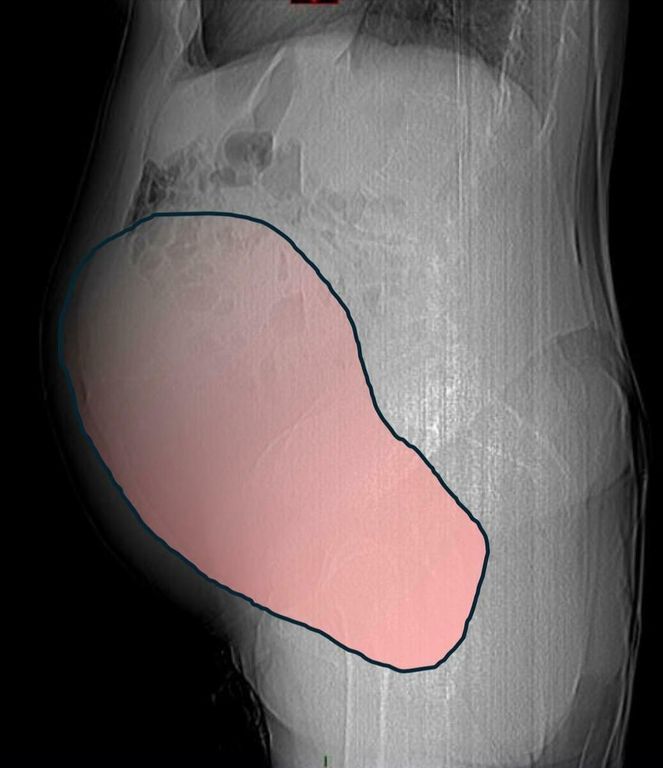

Per mesi la gigantesca cisti ovarica, con un diametro di circa 28 centimetri, è rimasta nascosta, senza dare segnali evidenti. La paziente non si era accorta di nulla. L’allarme è scattato quando la massa, associata alla presenza di una seconda neoplasia intestinale, ha iniziato a comprimere il colon, provocando sintomi acuti ed improvvisi fino ad una grave difficoltà intestinale non più ignorabile.

Durante l’intervento emerge tutta la gravità della situazione. La gigantesca neoplasia ovarica viene asportata: pesa circa 6 chilogrammi, con un volume paragonabile a quello di una gravidanza gemellare a termine. Ma non è l’unica minaccia. I sintomi più pericolosi sono legati alla sofferenza intestinale, che richiede un intervento immediato e coordinato di più specialisti.